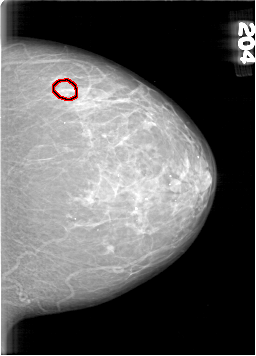

D_4098_1.LEFT_MLO

LEFT_MLO LINES 6841 PIXELS_PER_LINE 4636 BITS_PER_PIXEL 12 RESOLUTION 43.5 OVERLAY

FILE: D_4098_1.LEFT_MLO.OVERLAY

TOTAL_ABNORMALITIES 1

ABNORMALITY 1

LESION_TYPE CALCIFICATION TYPE AMORPHOUS DISTRIBUTION CLUSTERED

ASSESSMENT 0

SUBTLETY 3

PATHOLOGY BENIGN

TOTAL_OUTLINES 1

BOUNDARY

FILE: D_4098_1.LEFT_CC.OVERLAY